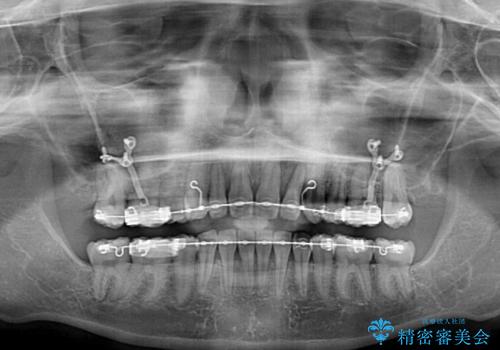

- 地元で抜歯治療を行っている途中、東京へ転職したため治療を継続して欲しいとのことで来院された患者様です。

出っ歯を抜歯矯正にて治療をしていらっしゃいましたが、抜歯スペースが少し残っていたため、閉じて歯列を仕上げていくこととしました。